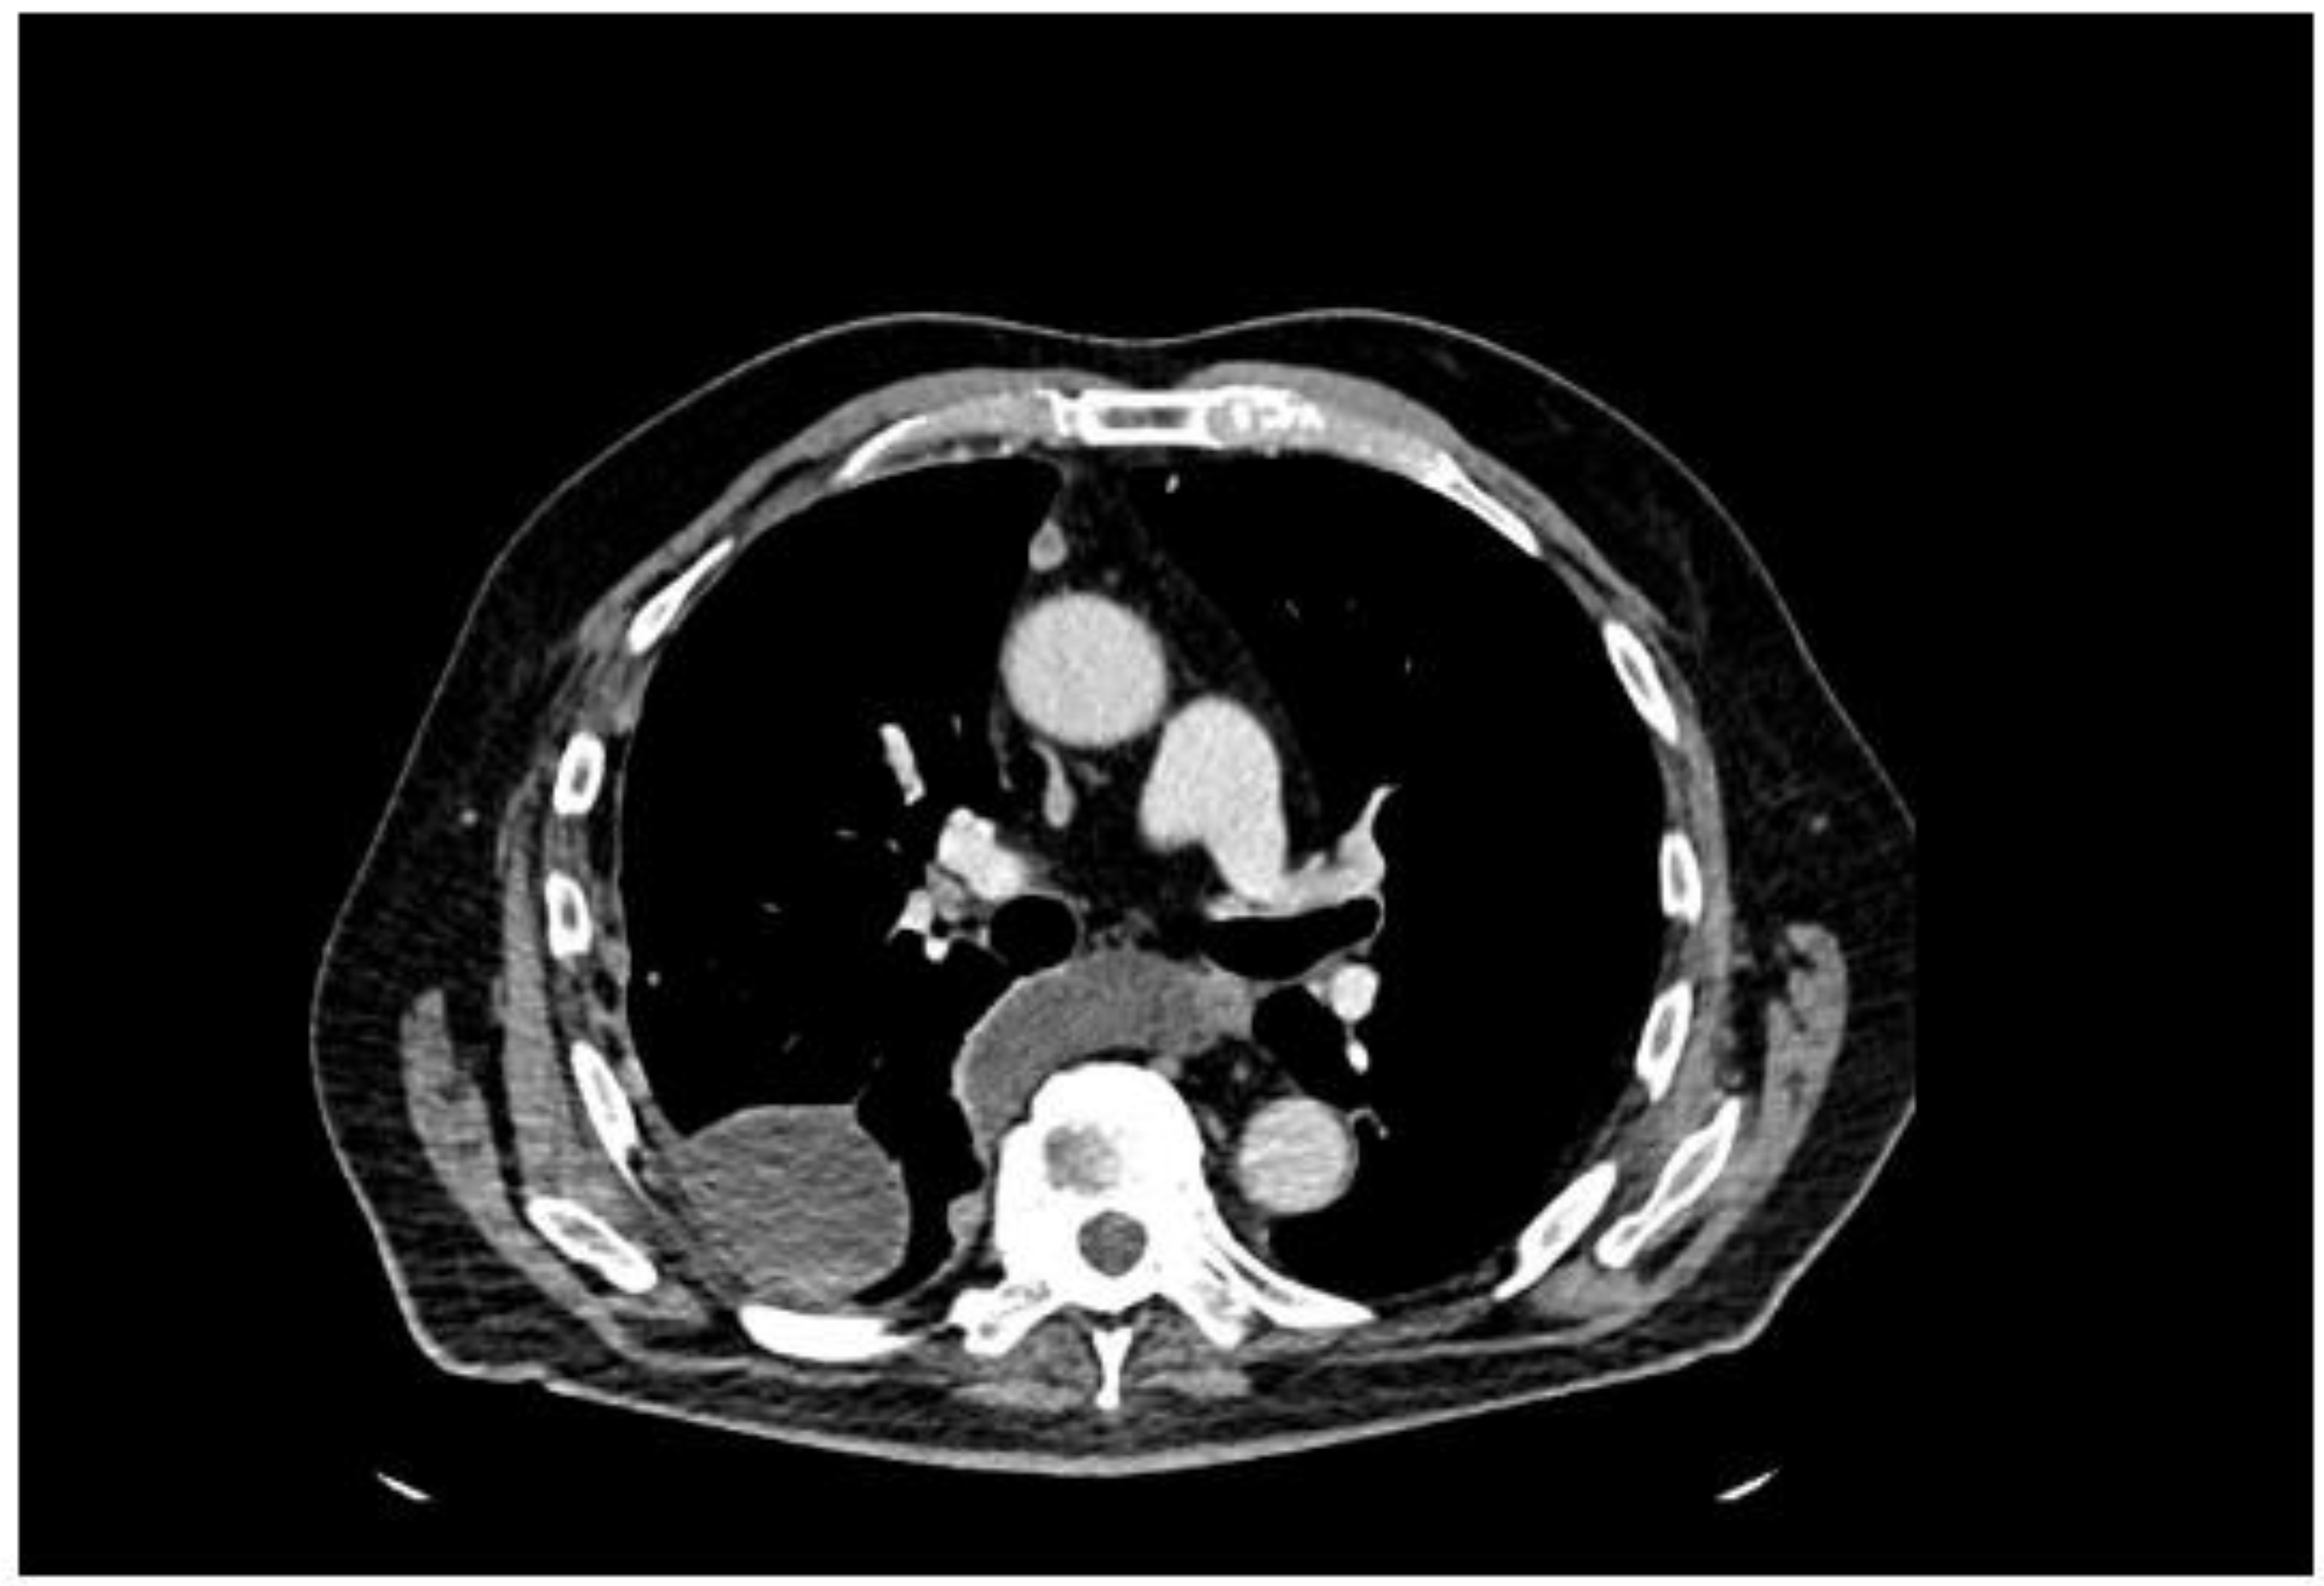

2. Case Presentation